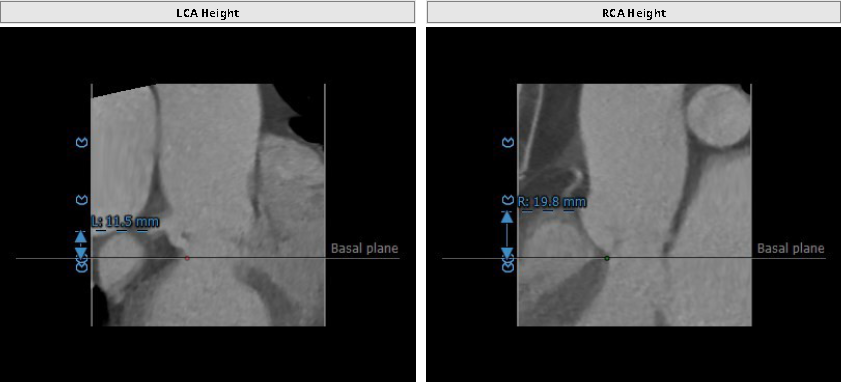

术前CT评估

瓣环平均直径:24.7 mm,左室流出道平均直径:24.3mm。

升主动脉增宽:42.6mm,最佳投射角度:LAO:9°Cranial:12°。

左冠开口高度:11.5 mm,右冠开口高度:19.8 mm。

瓣环平均直径:24.7mm,左室流出道直径24.3mm

窦管交界直径36.9mm,升主动脉直接42.6mm

左冠开口高度11.5mm,右冠开口高度19.8mm

最佳投射角度:LAO:9°Cranial:12°,瓣环、瓣叶及窦部无明显钙化